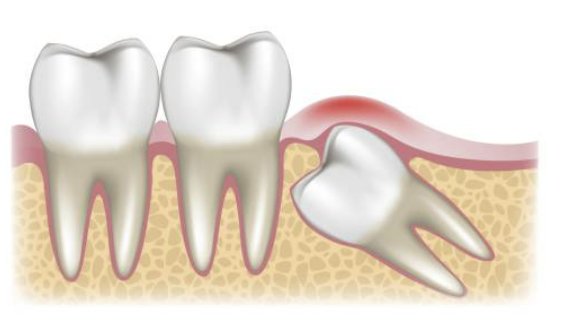

안녕하세요. 사랑니를 발치한 후에는 상처가 잘 아물도록 적절한 식습관을 유지하는 것이 매우 중요합니다. 무리한 식사는 출혈, 감염, 통증 등을 유발할 수 있으므로 주의해야 합니다. 지금부터 사랑니 발치 후 안전하게 식사하는 방법과 피해야 할 음식에 대해 자세히 알아보겠습니다.

사랑니 발치 후에는 상처 부위가 매우 민감하며 잘못된 식습관이 회복 속도를 늦출 수 있습니다. 올바른 식사 습관을 유지하면 통증을 줄이고 감염 위험을 낮추며 빠른 회복을 돕습니다.

빨대 사용 금지: 빨대로 음료를 마시면 음압이 발생하여 혈전이 빠질 위험이 있습니다. 이는 드라이소켓을 유발할 수 있으므로 반드시 피해야 합니다.